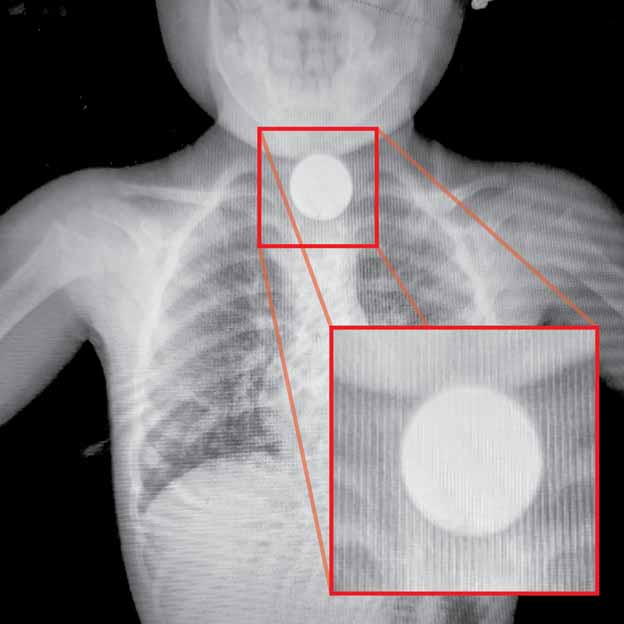

El Dr. Federico Schrodel, director del Hospital Regional de Ciudad del Este, manifestó que el día miércoles, siendo las 20:00 horas, se reportó el ingreso de una niña de 2 años de edad al Servicio de Urgencias del mencionado Hospital, a consecuencia de la ingestión accidental de un cuerpo extraño (moneda) que quedó alojado en su aparato digestivo, siendo luego derivada y asistida de urgencia por especialistas en gastroenterología de la Fundación Tesãi, ya que su vida corría serio peligro, según el informe.

“La moneda quedó en el esófago, por tal motivo nos comunicamos con el Dr. Fernando Bittinger quien autorizó la realización del procedimiento en la Fundación Tesãi. El encargado fue el Dr. Ángel Quiñónez con un equipo médico que procedió a la extracción de un cuerpo extraño, felizmente todo salió bien”, explicó el especialista.